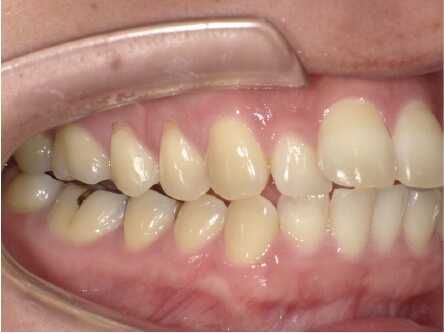

叢生の症例

41歳

/

女性

相談内容

横から見た時のガタガタが気になる

カウンセリング・診断結果

インビザライン、正中は上11に合わせていく、抜歯・拡大装置・IPR・アタッチメントOK

治療内容・方法

アライナー矯正

術後の経過・現在の様子

クリアライナー使用

治療のリスク

痛み・歯根吸収・歯肉退縮・虫歯・後戻り

費用・治療期間

880,000円、7ヶ月

トレーニングなど